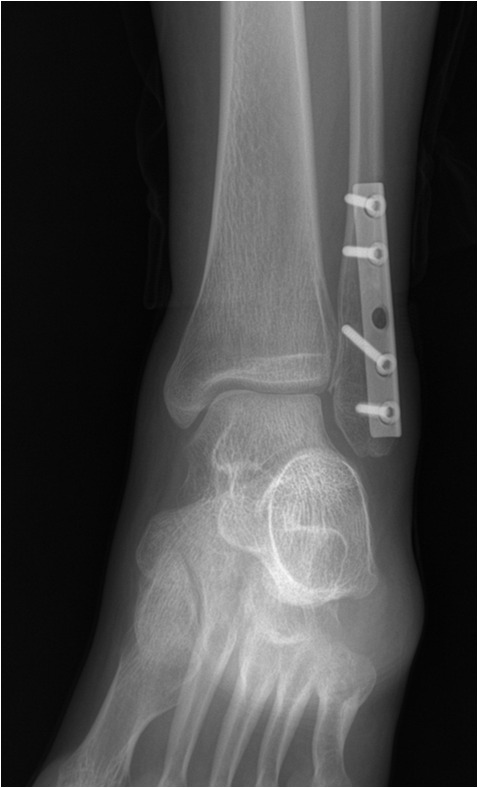

2010.4.30일에 인공 뼈 이식을 한 후 철판으로 고정하는 수술을 받았습니다.

수술후]